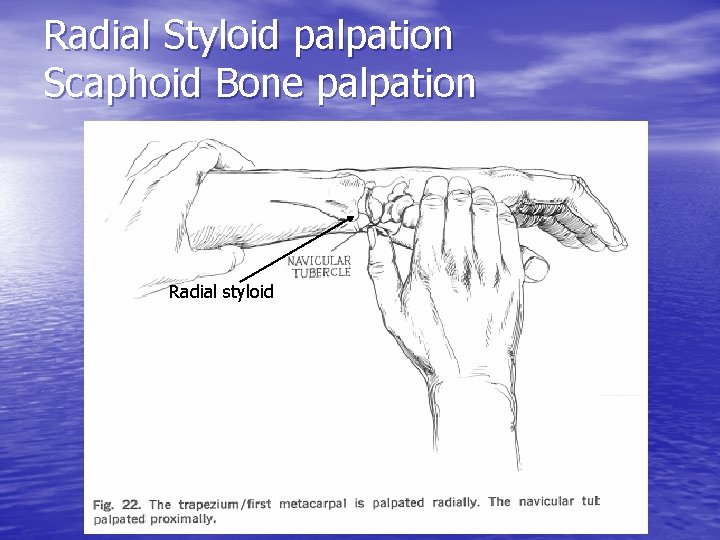

Radial Styloid palpation Scaphoid Bone palpation Radial styloid

Scaphoid Fracture • Most commonly fractured carpal bone – 70 -80% of all carpal bone injuries – 8% of all sports related fractures – 1 in 100 college football players • Most susceptible to injury – Bridges proximal and distal rows of the carpal bones – Load to the dorsiflexed wrist as in fall onto outstretched hand

Scaphoid Fracture • Painful, swollen wrist after a fall • Tenderness in snuffbox • High frequency of nonunion and avascular necrosis • Initial x-rays often unremarkable